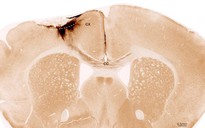

Tại Khoa Cấp cứu Bệnh viện Gia An 115, người bệnh có triệu chứng liệt nửa người trái, nghi ngờ đột quỵ. Qua chụp sọ não bằng máy CT siêu tốc, các bác sĩ khối xuất huyết lớn tại vùng trán – đỉnh bán cầu phải, kích thước 57x23x47mm, thể tích gần 40cm³, nghi do vỡ dị dạng động tĩnh mạch. Máu tụ trong não lan vào hệ thống não thất, gây phù não diện rộng, thoát vị liềm não, chèn ép… khiến bệnh nhân rơi vào hôn mê, nguy kịch.

Ngay lập tức, các bác sĩ chạy đua thời gian mổ khẩn cứu người. Sau phẫu thuật, não cô gái đã xẹp trở lại, khối máu tụ đã được lấy hết, dị dạng được cắt bỏ hoàn toàn, mô não đã được giải ép.